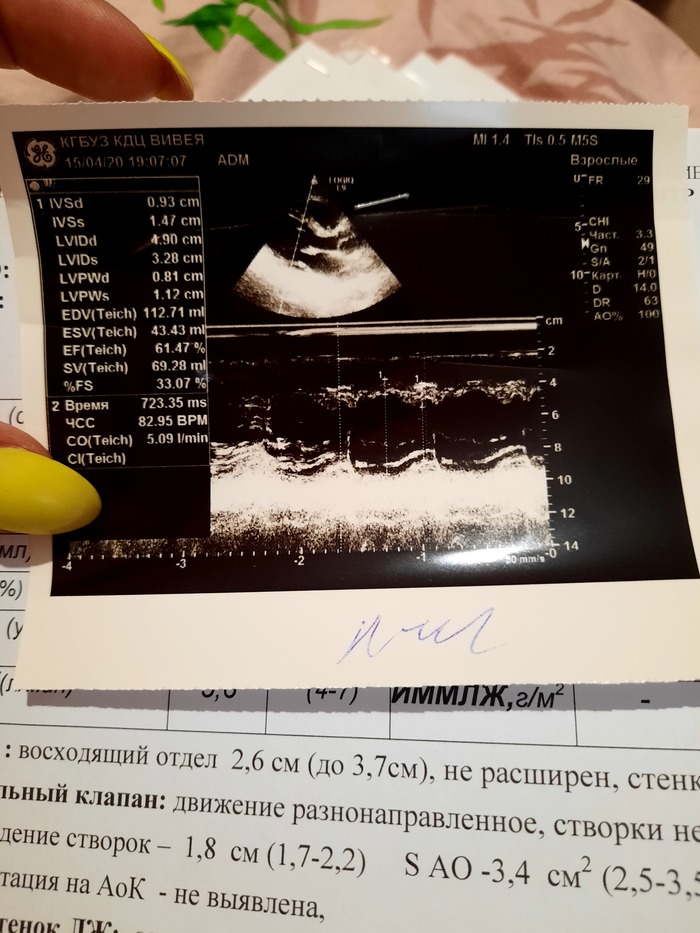

Прикладываю результаты, может кто нибудь сможет подсказать, как дальше быть?